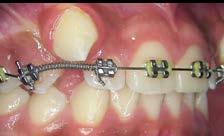

Los caninos retenidos constituyen una alteración eruptiva frecuente, con mayor prevalencia en la arcada superior. Su etiología es multifactorial y puede interferir con el trayecto normal de erupción, comprometiendo la oclusión y la estética.

Objetivo: Corregir una maloclusión Clase II división 2 mediante tratamiento ortodóntico en un paciente en crecimiento con ambos caninos superiores retenidos. Metodología: Se presenta el caso de un paciente masculino de 12 años, en dentición permanente, con perfil convexo, patrón dolicofacial y Clase II esquelética. Se realizó tratamiento ortodóntico sin extracciones. Para la tracción y alineación de los caninos retenidos se emplearon resortes abiertos (open coil springs) para la creación de espacio. Resultados: